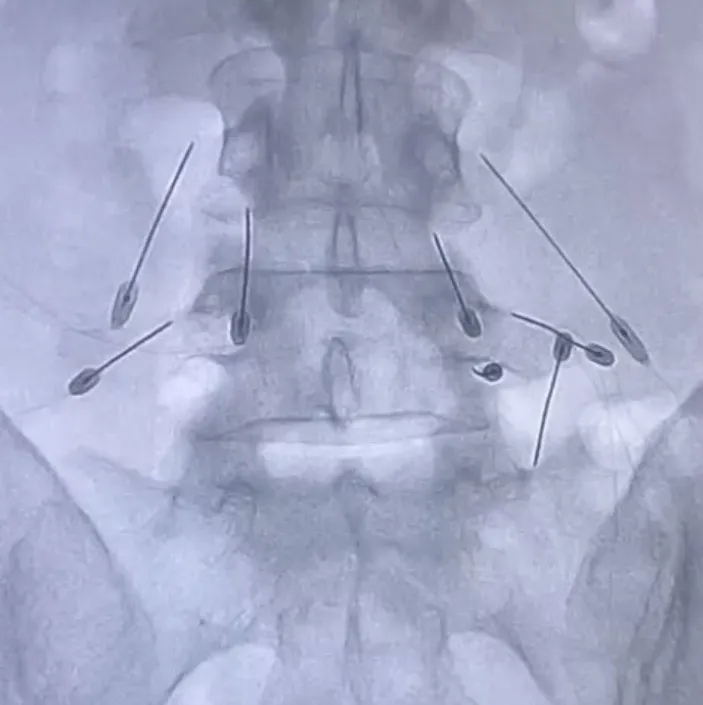

2. Setelah dilarikan ke rumah sakit dan menjalani pemeriksaan, diketahui bahwa Ferry Maryadi mengalami cedera yang cukup serius pada area tulang belakang.

3. Ia menjelaskan bahwa bagian L4 dan L5 di tulang belakangnya mengalami sobekan pada sendi yang memicu pembengkakan cukup parah.

4. Meski begitu, dokter menyebut kondisinya tidak separah yang dibayangkan, dan hanya butuh istirahat total.